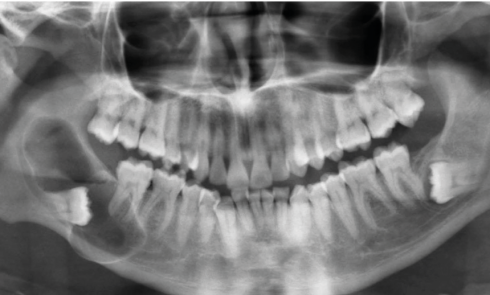

Présentation du cas Un patient âgé de 37 ans, en bonne santé (ASA 1), se présente en consultation. Il est...